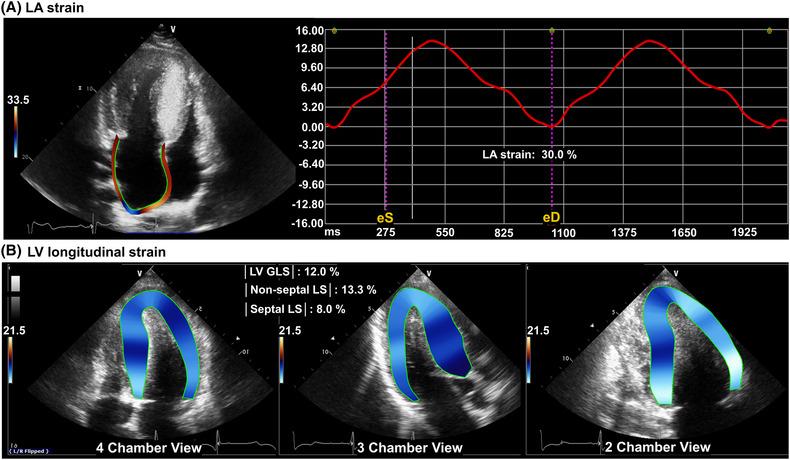

Among 65 patients who underwent septal myectomy for symptomatic obstructive HCM from 2006 to 2022, 44 were analysed after excluding those who underwent simultaneous valve repair or replacement or maze operation. LA and LV functional variables including LA strain and LV global longitudinal strain were evaluated by two-dimensional and speckle-tracking echocardiography and compared before and 1 year after surgery. After septal myectomy, LA volume index (58.1 ± 18.3 vs. 45.3 ± 14.6 mL/m , P = 0.001) decreased significantly. As LV end-systolic dimension increased after surgery, the LV ejection fraction decreased (73.8 ± 6.7 vs. 62.9 ± 8.3%, P < 0.001). LA strain (24.4 ± 9.3 vs. 30.5 ± 13.6%, P = 0.004) improved after septal myectomy, but LV global longitudinal strain deteriorated (-12.6 ± 3.6 vs. -11.6 ± 4.3%, P = 0.033), mainly related to worsening non-septal longitudinal strain (-14.4 ± 4.3 vs. -10.9 ± 8.4%, P = 0.005).

在2006年至2022年期间因有症状的梗阻性HCM接受间隔心肌切除术的65例患者中,排除那些同时进行瓣膜修复或置换或迷宫手术的患者后,对44例进行了分析。通过二维和斑点追踪超声心动图评估包括LA应变和LV整体纵向应变在内的LA和LV功能变量,并在手术前和手术后1年进行比较。间隔心肌切除术后,LA容积指数(58.1±18.3 vs. 45.3±14.6 mL/m²,P = 0.001)显著降低。由于手术后LV收缩末期内径增加,LV射血分数降低(73.8±6.7 vs. 62.9±8.3%,P < 0.001)。间隔心肌切除术后LA应变(24.4±9.3 vs. 30.5±13.6%,P = 0.004)有所改善,但LV整体纵向应变恶化(-12.6±3.6 vs. -11.6±4.3%,P = 0.033),主要与非间隔纵向应变恶化有关(-14.4±4.3 vs. -10.9±8.4%,P = 0.005)。